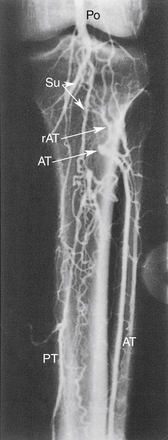

РИСУНОК 13-18. Окклюзию дистальной подколенной (Po) артерии можно обойти следующим образом: (1) икроножная (Su) и малая мышечная ветви → к возвратной передней большеберцовой артерии (rAT), которая кровоснабжает переднюю большеберцовую артерию (AT); (2) икроножная (Su) и малые мышечные ветви → к задней большеберцовой артерии (PT).